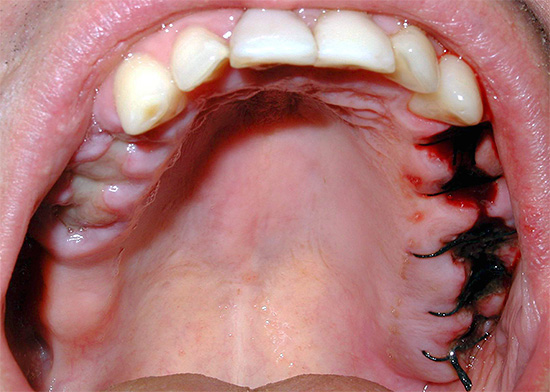

A convergência completa das bordas da ferida com uma extração dentária realizada qualitativamente ocorre normalmente em 2-2,5 semanas. Simultaneamente à epitelização, ocorrem a formação de feixes ósseos e o desenvolvimento de ossos jovens.

Com um dente traumaticamente rasgado (quando os tecidos circundantes são esmagados e rasgados), a cicatrização das gengivas se estende por um longo tempo, porque após a remoção ocorre uma laceração, cujas bordas estão frequentemente muito afastadas e as seções dos alvéolos (osso) e da lacuna do septo inter-radicular, não cobertas pela margem gengival. Quando a inflamação do tecido ocorre dentro e ao redor do poço, as bordas da ferida não se juntam por muito tempo e a epitelização não termina após 2 semanas, mas pode levar de 30 a 50 dias.

Somente após 4-5 meses, a formação de tecido ósseo jovem é concluída e a versão final da "cobertura" gengival é formada sobre o orifício.